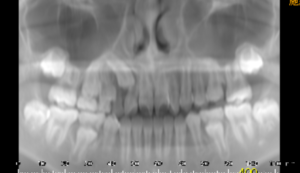

「上顎犬歯埋伏のCT画像」